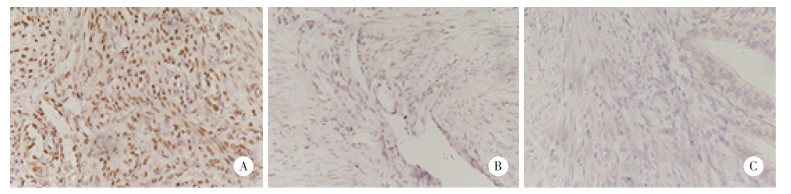

2 结果 2.1 子宫内膜组织中ZIC4的表达ZIC4蛋白主要表达于子宫内膜组织细胞核中,阳性表达呈棕黄色、棕褐色均匀颗粒状或片状。免疫组化结果显示,子宫内膜癌组ZIC4阳性率[94.5%(104/110)]和非典型增生组阳性率[55%(11/20)]显著高于正常对照组[23.3%(7/30)](P < 0.001,P = 0.022 3)。见图 1。

|

| A, endometrial cancer; B, atypical hyperplasia; C, normal endometrium secretory phase. 图 1 ZIC4在各组子宫内膜组织中的表达SP×400 Fig.1 ZIC4 expression in the endometrial tissue from each group SP×400 |